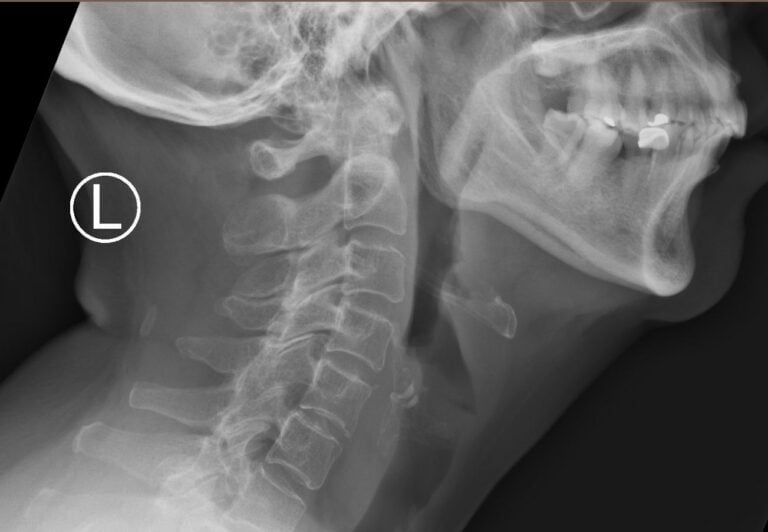

This patient was seen by us in the Accident & Emergency Department. He did not complain of any overt swallowed fish bone symptoms except for mild throat discomfort. An X-ray of the neck showed no fish bone in the throat. Examination of the mouth and the region of the tonsils revealed no fish bone in the throat. However, it is routine to perform flexible nasoendoscopy (putting a small flexible camera) down the nose and deeper down the throat, to rule out any fish bone in the throat further down, or foreign body lodged in the throat. This procedure revealed a fish bone lying horizontally, stuck at the back of the tongue, in front of the voice box. This would not have been seen with a routine examination of the mouth and oral cavity.

- A neck X-ray taken from the side to see if there is a bone in the throat